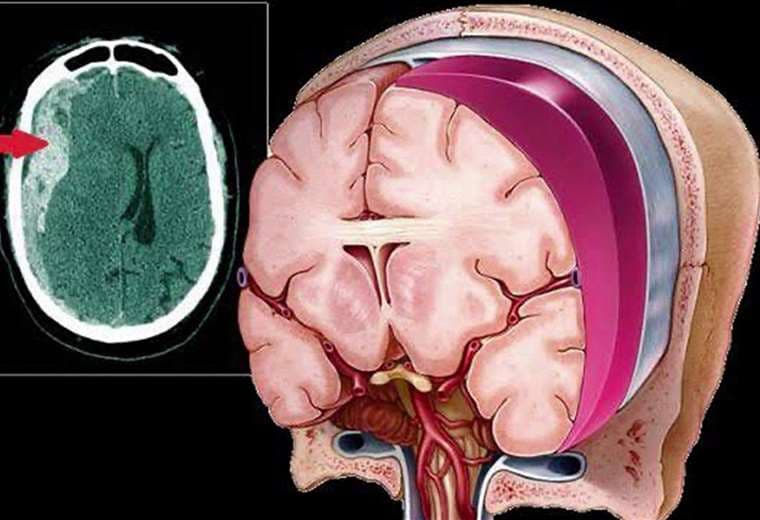

El hematoma subdural, una acumulación de sangre entre el cerebro y el hueso del cráneo, se presenta con cada vez más frecuencia entre los adultos mayores de 60 años.

En nuestro país, alrededor de 260 mil personas enfrentan el riesgo de desarrollar este trastorno neurológico, especialmente debido a caídas y al uso de medicamentos anticoagulantes.